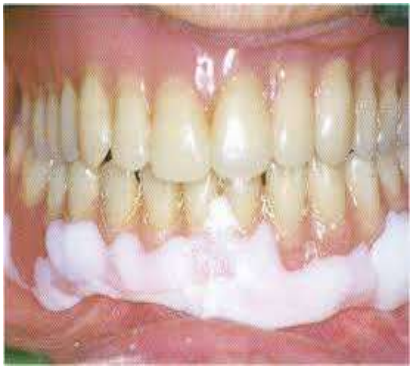

- Confection de couronnes provisoires (temporisation entre la préparation et la prothèse définitive)

Prise en charge : Le praticien opte pour une réparation à la résine auto-polymérisable. Les deux fragments sont repositionnés avec précision, les surfaces de fracture sont mordancées mécaniquement, puis la résine est coulée en fine couche. La polymérisation est complète en moins de 10 minutes à température ambiante.

Résultat attendu : La prothèse réparée est rendue à la patiente le jour même. Elle est fonctionnelle mais temporaire. Une refabrication ou une réparation définitive en laboratoire est programmée dans la semaine.

Point pédagogique : Ce cas illustre l’intérêt pratique des résines auto-polymérisables pour les réparations d’urgence. Leur prise chimique rapide sans équipement thermique est un atout décisif en conditions de cabinet.